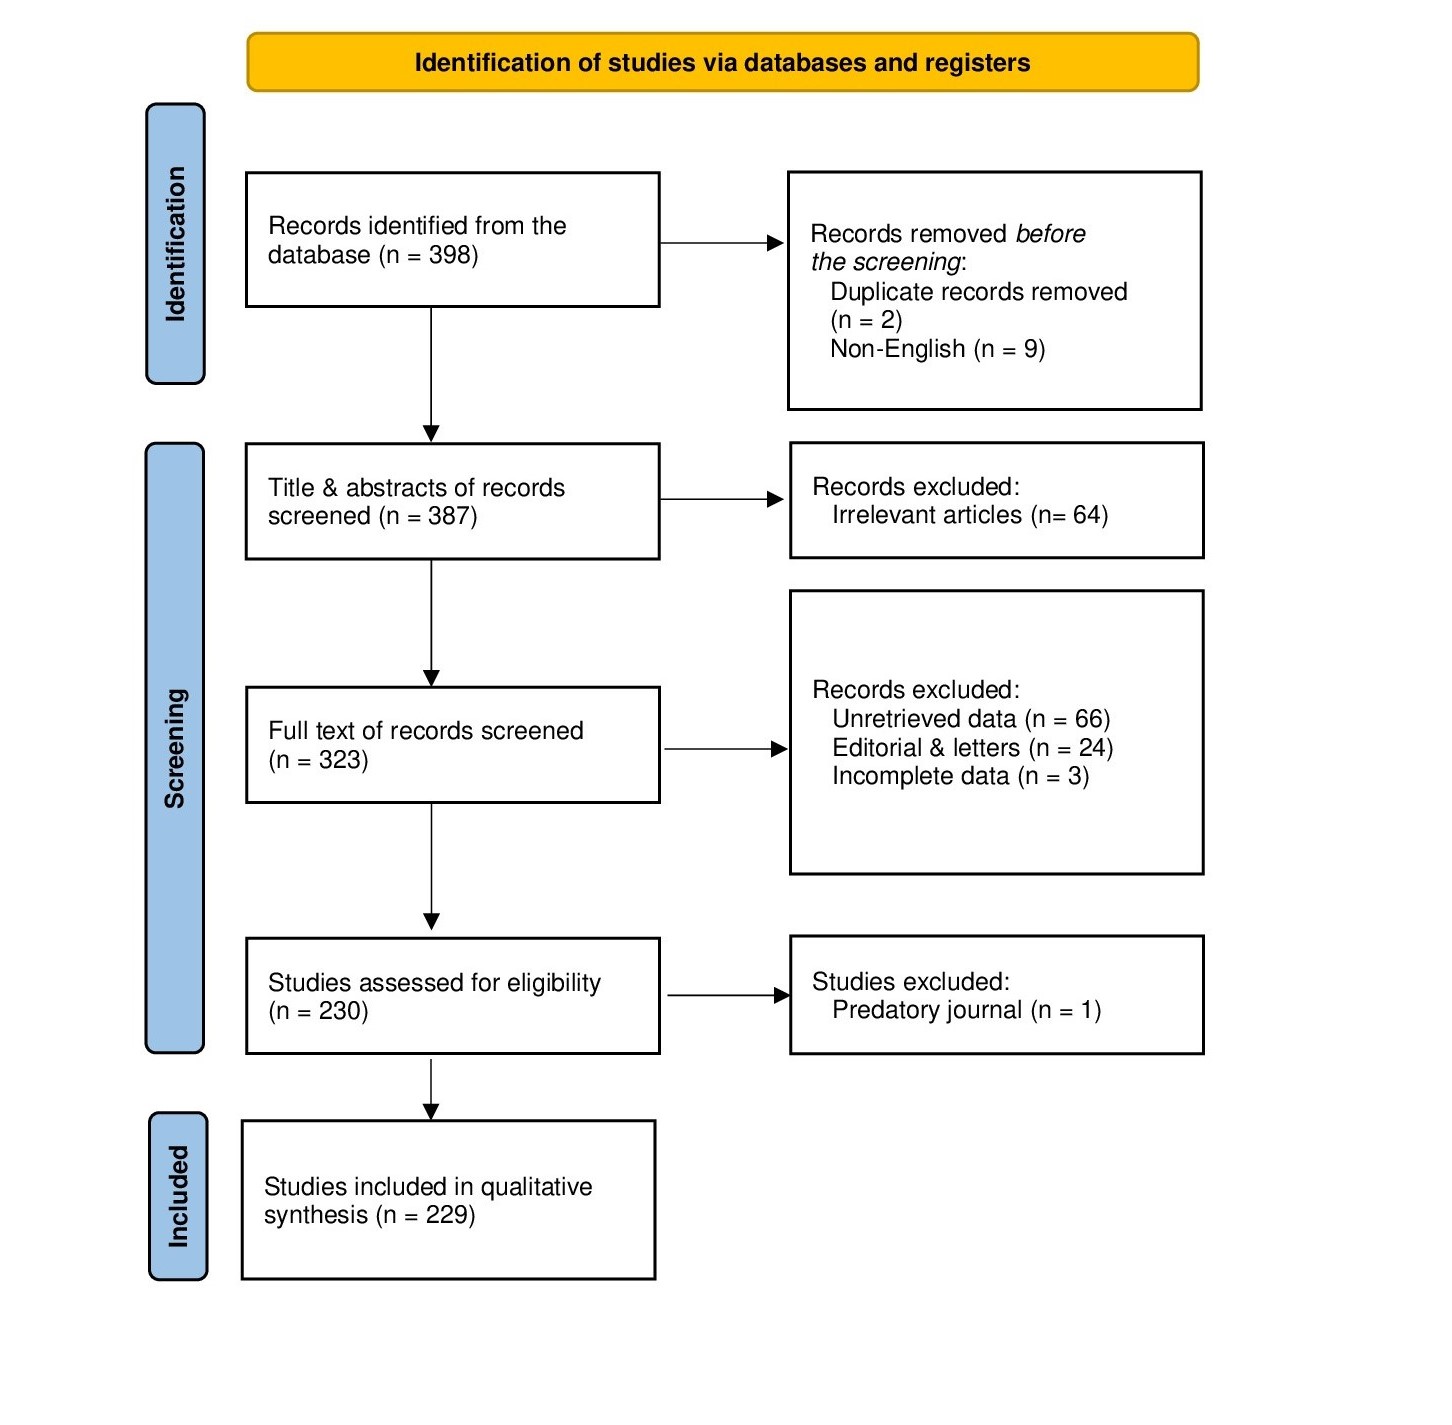

A total of 398 articles were identified through the search. After an initial review, 11 articles were excluded due to duplication and non-English language. The remaining 387 articles underwent title and abstract screening, during which 64 articles were excluded for not meeting the inclusion criteria. Consequently, 323 articles proceeded to full-text screening, and 93 were excluded due to unretrievable data, editorials, letters, or incomplete information. The remaining articles were then assessed for eligibility, resulting in 229 articles [1, 3, 4, 6-231] with 1,002 patients meeting the inclusion criteria and included in the study [Fig. 1].